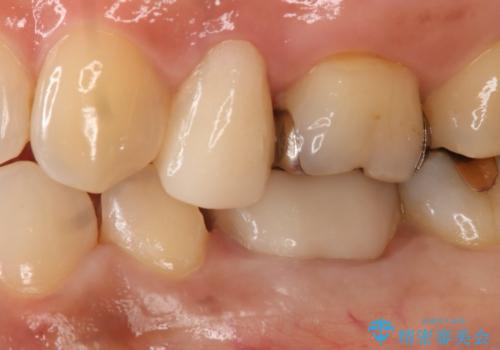

- 左下5番の銀歯をセラミックにやり変え希望の患者様です。

切削量を考慮し、セラミックインレーでの治療を選択しました。

銀歯直下のう蝕を除去しCRで裏層を行った上で、形成・印象を行っています。